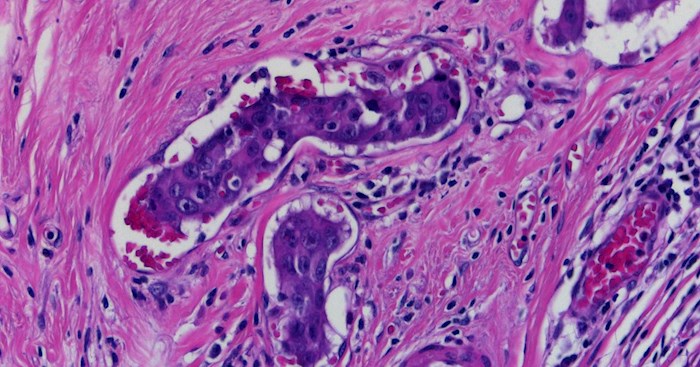

While he recognises sex as biology, for example in relation to the difference in the incidence of breast cancer in men compared to women, and in women compared to men in prostate cancer (in women’s Skene’s glands), he disagrees that sex is defined by biology or that there are only two sexes. In justification he points to intersex people, ignoring that differences/disorders in sexual development (DSDs) are a biological phenomenon and people with DSDs are either male or female and not a third sex.